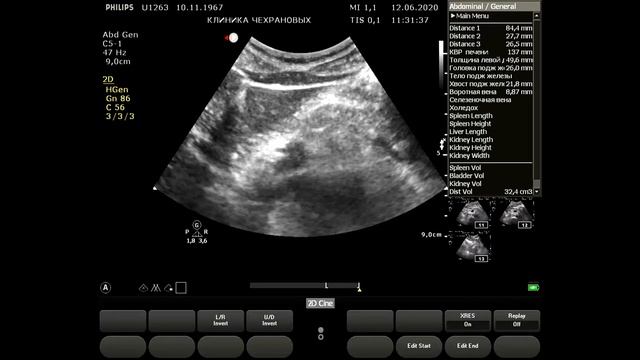

2020061211230694 УЗИ органов брюшной полости

Смотреть

Чехранов Андрей: Вези в УЗИ

2024-12-18 в 10:39:03